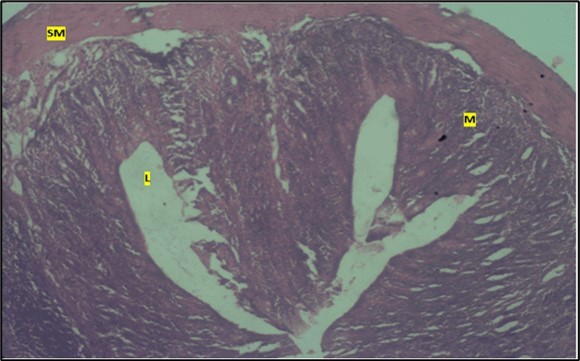

Results from the large intestine histological observation showed normal appearance of epithelial cells lining the mucosa with no pathological observations in control animals (Figure 5). However, administration of Abelmoschus esculentus at low dose showed dysplasia of cells and loss of normal epithelial shape (Figure 6) and the high dose group showed mild dysplasia (Figure 7)

Figure 7.High dose showing the lumen (l), the smooth muscle layer(sm). mucosa (m) shows mild dysplasia H & E. X40.